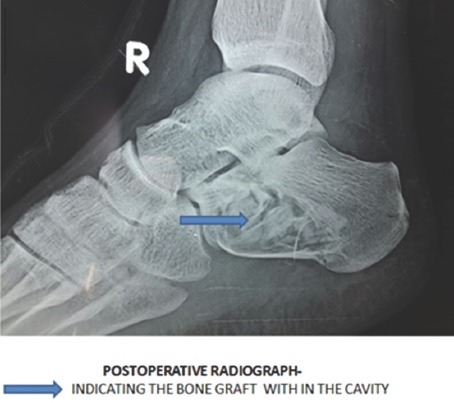

A differential diagnosis of aneurysmal bone cyst or giant cell tumor with pathological fracture was made. Under spinal anesthesia and strict aseptic precautions, the lesion was curetted and the cavity was filled with iliac bone grafts (Fig. 3 and 4). The curetted specimen was sent again for histopathological examination, and the diagnosis was confirmed (Fig. 5). The wound was closed, dressed, and below knee posterior plaster slab was applied.

Figure 4.

Post-operative X-ray.